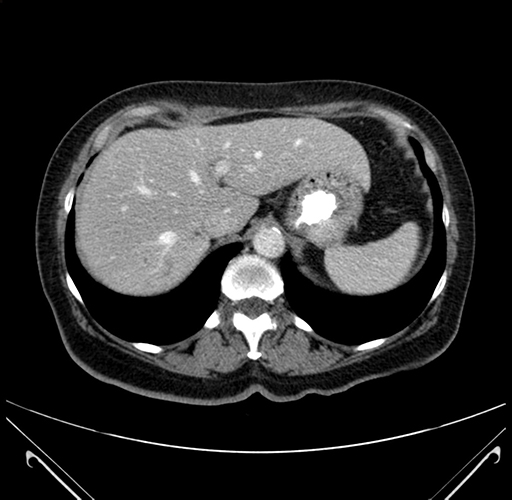

Axial Venous